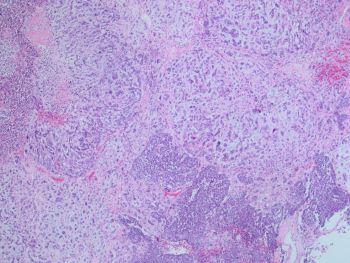

Answer: C. Mixed Mullerian tumor/carcinosarcoma. Sections from the tumor show biphasic, malignant tumor with high-grade epithelial and sarcomatous components consistent with carcinosarcoma.

Histopathology: The tumors are composed of an admixture of malignant epithelium and mesenchyme, which is typically sharply juxtaposed. The carcinomatous component often shows endometrioid or serous differentiation, but clear cell and undifferentiated carcinoma may be encountered. The mesenchymal component most commonly consists of high-grade sarcoma NOS, but heterologous elements (including rhabdomyosarcoma, chondrosarcoma, and rarely osteosarcoma) may be seen